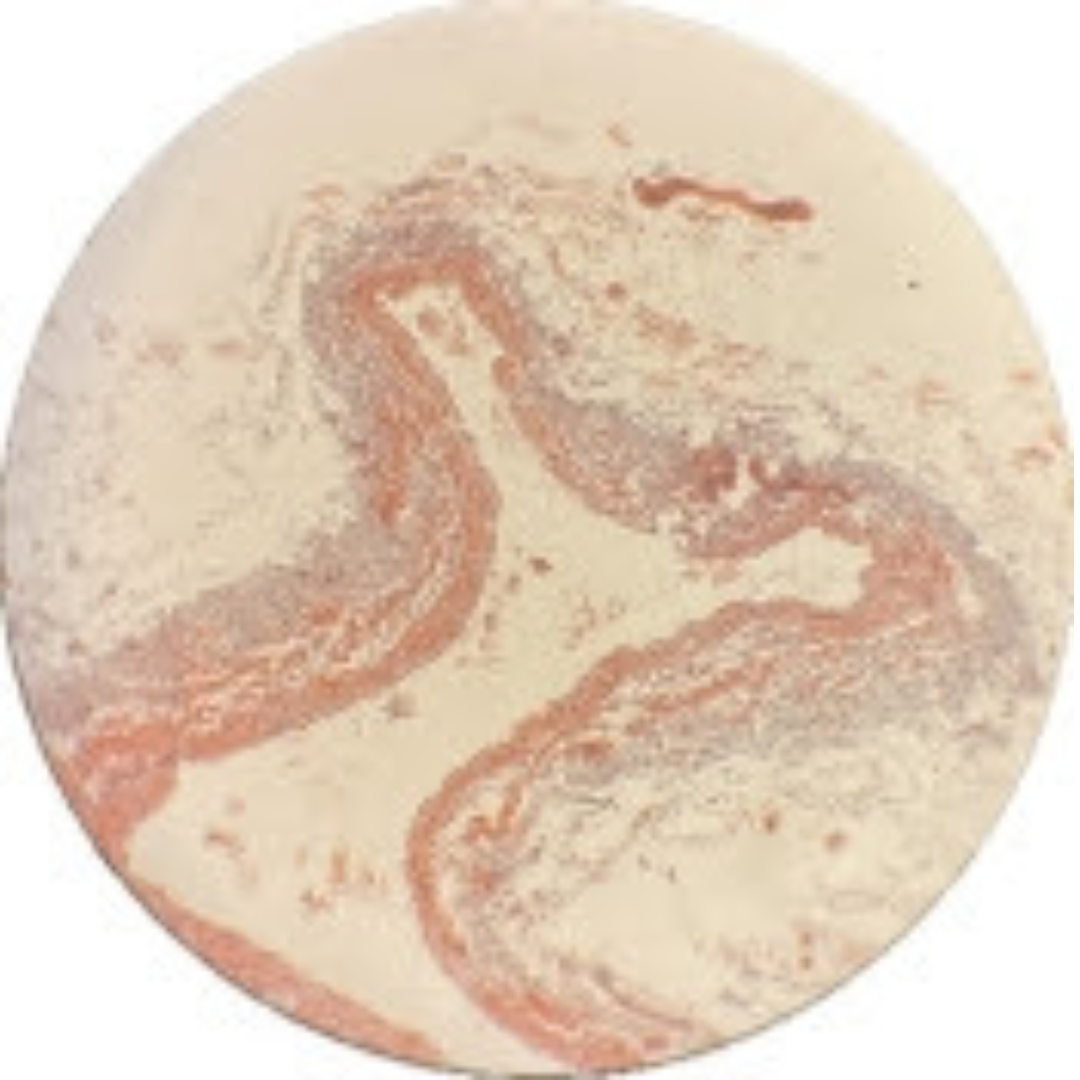

Muscular Arteries (Medium Sized Arteries)

Muscular Arteries (Medium Sized Arteries)

Muscular Arteries (Medium Sized Arteries)